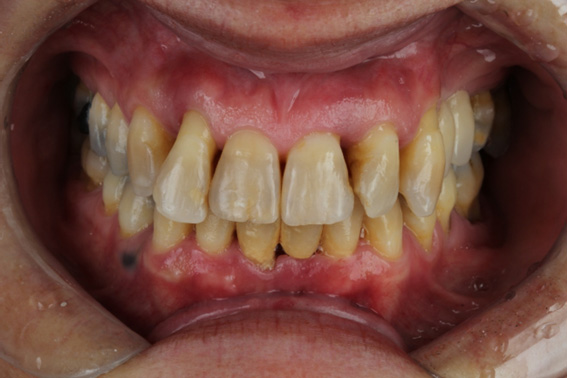

1 | Initial aspect, teeth in occlusion

2 | Initial aspect, lower elements